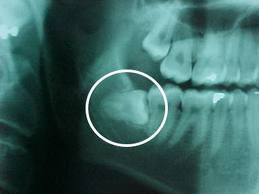

Răng khôn là chiếc răng mọc sau cùng  (mọc vào khoảng từ 18 đến 25 tuổi). Khi 28 chiếc thông thường đã mọc đủ trên cung hàm rồi, nếu

còn chỗ thì 4 chiếc răng cuối cùng này sẽ được mọc lên ngay thẳng cùng các răng khác. Nếu chẳng may trên mỗi hàm, 14 răng đã tự điều

chỉnh đủ chỗ thì 2 răng khôn 2 bên sẽ không có đường mọc lên thì nó sẽ tự tìm đường khác để mọc ra.

Ảnh minh họa